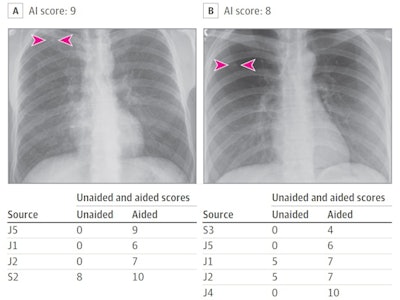

Images were selected to represent nodules with different levels of detection difficulties (from easy to difficult). Two thoracic radiologists established the ground truth and nine junior and senior radiologist readers from Germany and the U.S. independently reviewed all images in two sessions, unaided and AI-aided.

Results showed the mean detection accuracy across all nine radiologists improved by 6.4% with AI-aided interpretation compared with unaided interpretation. Partial AUCs within the effective interval range of a 0 to 0.2 false-positive rate improved by 5.6% with AI-aided interpretation.

In addition, junior radiologists saw greater improvement in sensitivity for nodule detection with AI-aided interpretation as compared with their senior counterparts (12% vs. 9%), while senior radiologists experienced similar improvement in specificity (4%) as compared with junior radiologists (4%).